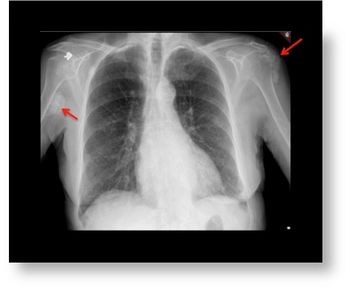

Image IQ: 74 y/o; Lump over right axillary region

ByEduardo Lacayo, MD,Erini Makariou, MD

A 74-year-old female presents with palpable lump over the right axillary region.